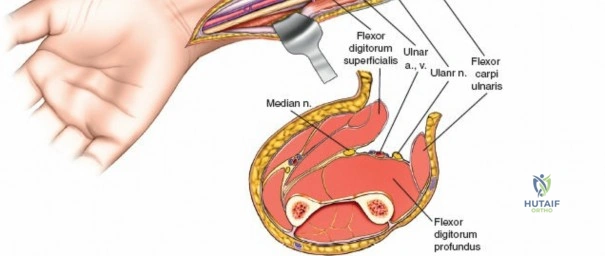

The Internervous Planes of the Forearm

The anterior approach to the radius is an elegant example of utilizing true internervous planes to achieve deep exposure without denervating musculature. Distally, the internervous plane lies between the brachioradialis muscle (innervated by the radial nerve) and the flexor carpi radialis muscle (innervated by the median nerve). Proximally, the plane transitions to lie between the brachioradialis (radial nerve) and the pronator teres muscle (median nerve). Exploiting this plane allows the surgeon to mobilize the entire lateral muscular compartment (the "mobile wad" comprising the brachioradialis, extensor carpi radialis longus, and extensor carpi radialis brevis) away from the anterior flexor compartment.

The Posterior Interosseous Nerve (PIN)

The posterior interosseous nerve is the single most important structure left vulnerable during exposure of the proximal radius. A branch of the radial nerve, the PIN dives into the supinator muscle through the Arcade of Frohse. It travels obliquely and spirally around the radial neck and proximal shaft within the substance of the supinator. In approximately 25% of patients, the nerve comes into direct contact with the posterior periosteum of the radial neck. Therefore, any blind placement of retractors around the posterior aspect of the proximal radius is strictly contraindicated, as it can easily crush the nerve against the bone, resulting in devastating loss of finger and thumb extension.

Superficial Surgical Dissection and Internervous Plane

Incise the deep fascia of the forearm in line with the skin incision. The initial goal is to identify the medial border of the brachioradialis as it courses down the forearm. It is a common pitfall to search for this border too far laterally. At the level of the elbow, the brachioradialis is expansive and extends almost halfway across the anterior forearm. It is surprisingly easy to mistake the plane between the brachioradialis and the extensor carpi radialis longus for the correct intermuscular plane.

To confirm the correct plane, look for the superficial branch of the radial nerve. This sensory nerve runs on the undersurface of the brachioradialis muscle. Once the true medial edge of the brachioradialis is found, develop the plane between it and the pronator teres (proximally) or the flexor carpi radialis (distally). Retract the brachioradialis laterally, taking care to keep the superficial radial nerve attached to its undersurface to protect it from traction injury.

Deep Surgical Dissection: Exposing the Proximal Third

Exposing the proximal third of the radius requires extreme vigilance due to the proximity of the posterior interosseous nerve. The key anatomical landmark here is the insertion of the biceps tendon. Follow the biceps tendon distally to its insertion on the bicipital tuberosity of the radius. A small bursa lies just lateral to the tendon; incise this bursa to gain initial access to the proximal radial shaft. Because the radial artery lies superficial and medial to the tendon at this level, all deep dissection must remain strictly lateral to the biceps tendon.

The proximal radius is draped by the supinator muscle. The PIN passes directly through the belly of the supinator. To protect the nerve, the forearm must be fully supinated. Supination dynamically rotates the radius, carrying the insertion of the supinator anteriorly and simultaneously displacing the PIN laterally and posteriorly, safely away from the surgical field.

With the forearm fully supinated, identify the broad insertion of the supinator on the anterior aspect of the radius. Incise the supinator directly along the line of its insertion onto the bone. It is critical to detach the muscle by dividing its insertion sharply at the bone, rather than splitting the muscle belly, which would risk cutting the PIN.

Proceed with strict subperiosteal dissection, elevating the supinator laterally off the bone. This is one of the rare instances in orthopedic surgery where the safety gained by staying in a subperiosteal plane completely outweighs the theoretical vascular damage to the bone caused by periosteal stripping. The elevated supinator muscle belly now acts as a protective cushion for the PIN.